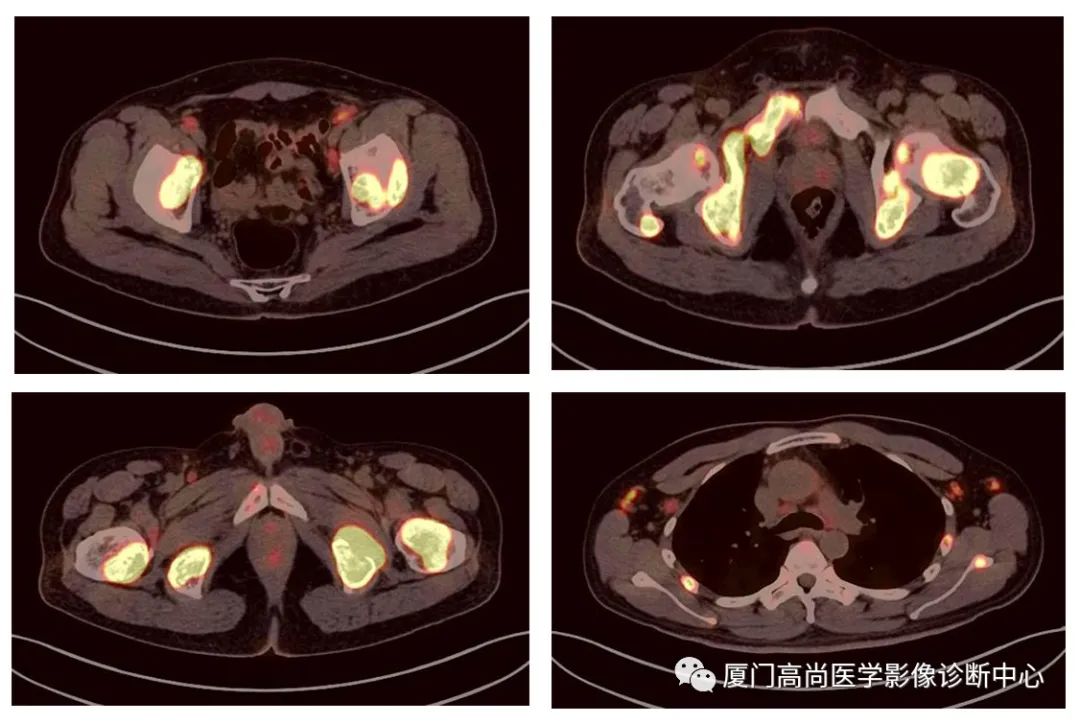

病例2、某女士,62歲,近3個月來自覺消瘦,無其他自覺癥狀,CT發(fā)現(xiàn)雙側(cè)腎上腺增大,性質(zhì)待定,查血各項腫瘤標(biāo)記物均正常,臨床診斷不清,申請做PET/CT檢查

雙側(cè)腎上腺病灶、膽囊病灶

腹腔淋巴結(jié)腫大

小腸多段淋巴瘤病灶

PET/CT發(fā)現(xiàn) :左心房、右心房見團塊狀FDG攝取增高;雙側(cè)腎上腺增大,F(xiàn)DG攝取增高;膽囊和胃壁結(jié)節(jié)樣FDG攝取增高;小腸多節(jié)段腸壁增厚,F(xiàn)DG攝取增高;腹膜后、腹腔及盆腔多發(fā)淋巴結(jié)腫大,F(xiàn)DG攝取增高;上述考慮為淋巴瘤

經(jīng)腎上腺穿刺活檢 :病理證實為彌漫大B細(xì)胞淋巴瘤